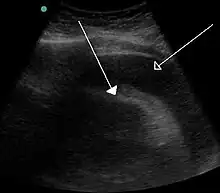

Echocardiogram (ultrasound): when pericardial effusion is suspected, echocardiography usually confirms the diagnosis and allows assessment of the size, location and signs of hemodynamic instability.[4] A transthoracic echocardiogram (TTE) is usually sufficient to evaluate pericardial effusion and it may also help distinguish pericardial effusion from pleural effusion and MI. Most pericardial effusions appear as an anechoic area (black or without an echo) between the visceral and the parietal membrane.[1] Complex or malignant effusions are more heterogeneous in appearance, meaning they may have variations in echo on ultrasound.[5] TTE can also differentiate pericardial effusion based on the size. Although it's difficult to define size classifications because they vary with institutions, most commonly they are as follows: small <10, moderate 10–20, large >20.[5] An echocardiogram is urgently needed for evaluation when there is concern for hemodynamic compromise, a rapidly developing effusion or history of recent cardiac surgery/procedures.[1]

A CT scan showing a pericardial effusion A large anechoic (black) pericardial effusion as seen on ultrasound. Closed arrow: the heart, open arrow: the effusion

A large anechoic (black) pericardial effusion as seen on ultrasound. Closed arrow: the heart, open arrow: the effusion Pericardial effusion due to malignancy. Note bulbous heart and primary lung cancer in right upper lobe.